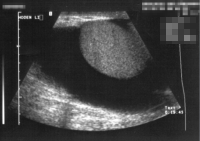

Die Abbildungen zeigen kindliche Hydrozelen (primäre) bzw. eine im Erwachsenenalter unklarer Genese (Abbildung 4abc).

DiaphanoskopieDiaphanoskopieDie Diaphanoskopie ist eine einfache klinische Untersuchung zur Abgrenzung der Hydrocelen von anderen skrotalen Raumforderungen. Bei Aufsetzen einer Untersuchungslampe auf das Skrotum schimmert der flüssigkeitsgefüllte Raum rötlich, bei solidem Skrotalinhalt liese sich das Skrotum jedoch nicht durchstrahlen. sowie die Sonographie (Abbildung 5).